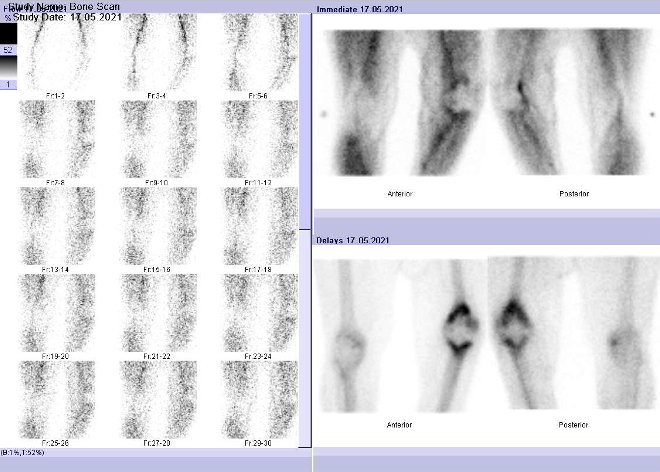

3fázová scintigrafie skeletu:

Na hybridní tomografické scintilační kameře Symbia T2 firmy Siemens byla

provedena třífázová scintigrafie kolenních kloubů po i.v. aplikaci bolu (v

malém objemu) 700 MBq 99mTc-oxidronátu (přípravek TechneScan HDP firmy Mallinckrodt Medical), dále celotělové scintigramy. Vyšetření

jsme doplnili o cílenou tomografickou scintigrafii (SPECT) kolenních kloubů a

přilehlé částí stehen a bérců kombinovanou s CT (obr. 1-3).

/ Obr. č. 1: 3fázová scintigrafie kolenních kloubů.

Popis: zvýšená perfuze v levém kolenním kloubu. Ložiska vyšší osteoblastické aktivity v levém kolenním kloubu (distální část stehenní a proximální část holenní kosti), obratli Th6, pravé části L5, ramenních kloubech, vnitřním kotníku LDK, nártech, levé části dolní čelisti při degenerativních a zánětlivých změnách, možné zubní afekci a susp. zánětlivém postižení levého kolenního kloubu. K potvrzení zánětu levého kolena jsme pacienta objednali k vyšetření značenými monoklonálními protilátkami proti granulocytům.